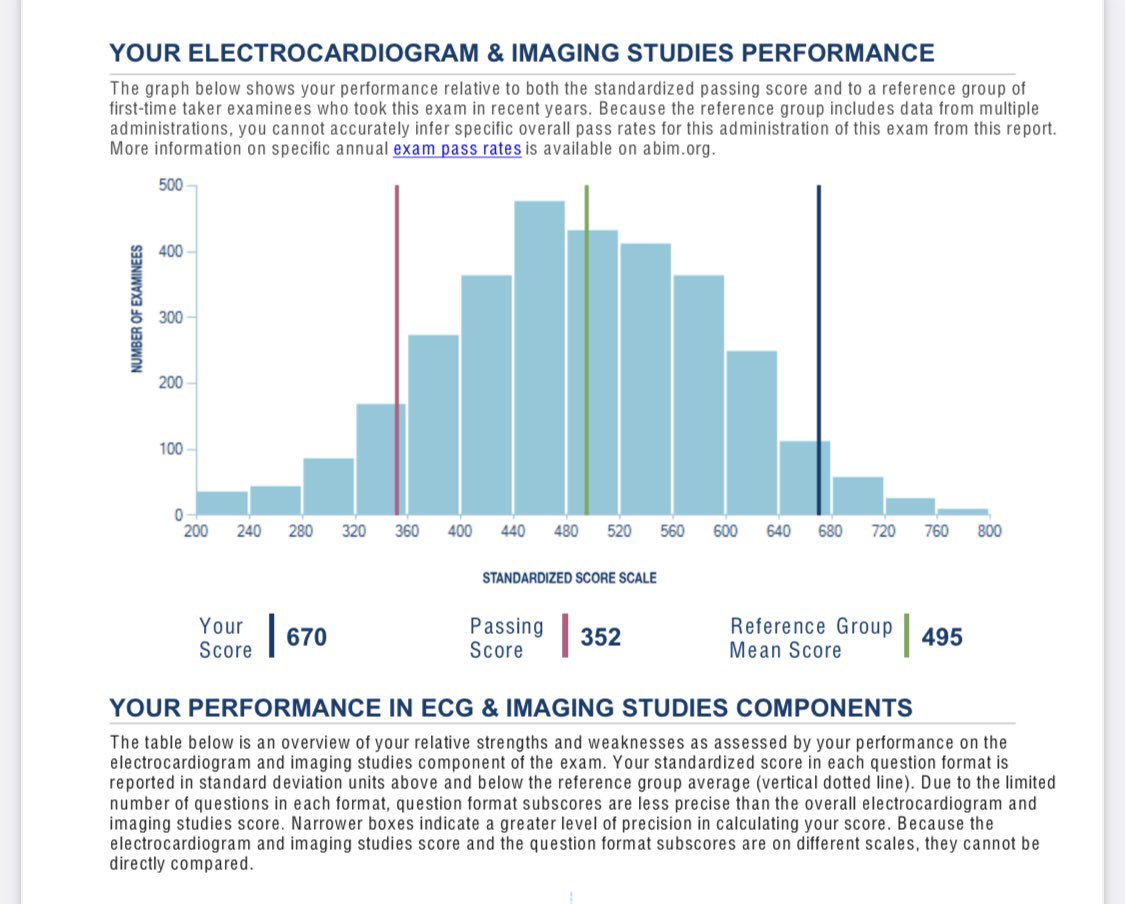

Board Certified Cardiologist 👩🏻⚕️🫀 Nailed the coding day 😉#CardiologyBoards ✅ Summa Health